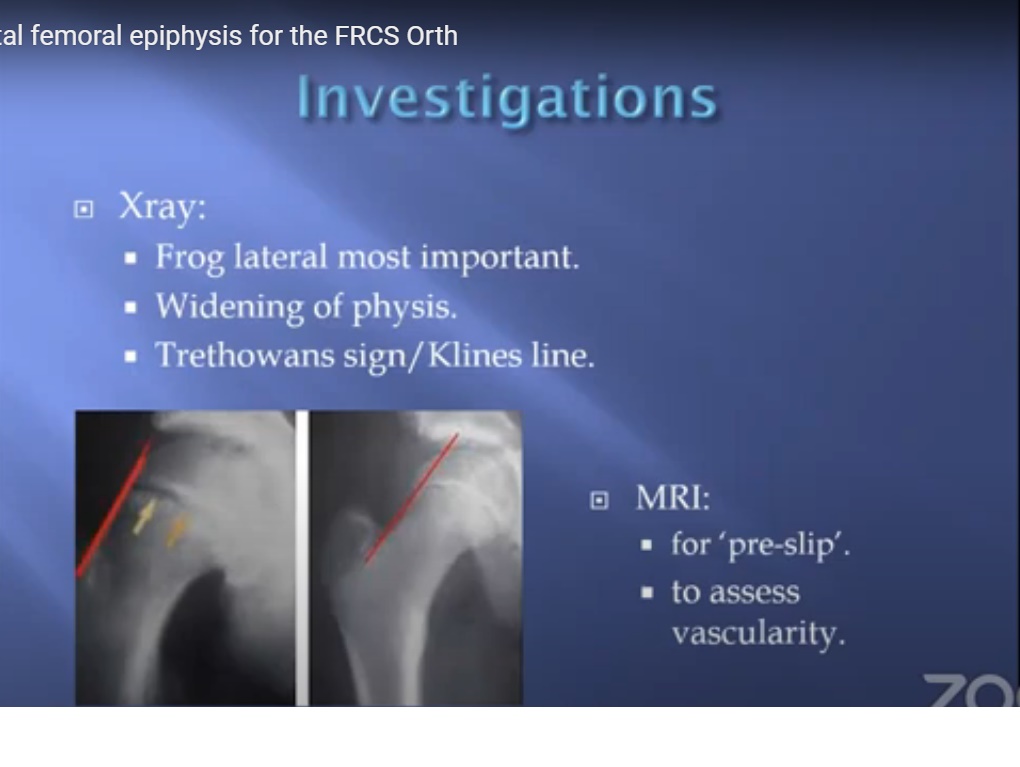

Slipped Femoral Epiphysis - YouTube

www.youtube.com

www.youtube.com

epiphysis slipped femoral